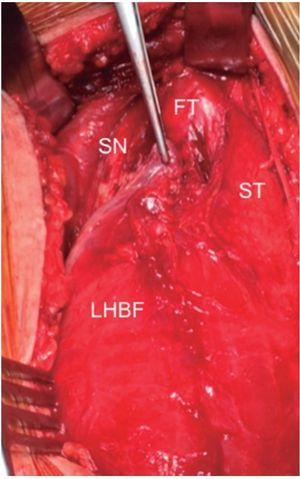

Figura 1 Las imágenes coronal y axial en T2 con saturación grasa del isquiotibial izquierdo muestran rotura parcial de fibras en la UMT proximal de PLBF representadas por un área de alta intensidad de señal adyacente a la UMT (flecha). Se observa también rotura de algunas fibras del semitendinoso (+). Vientre muscular semitendinoso (ST), porción proximal del bíceps femoral largo (long head biceps femoris [LHBF]), tendón semimembranoso (punta de flecha) y nervio ciático (*). En el corte coronal se observa edema muscular de patrón en pluma de ave.